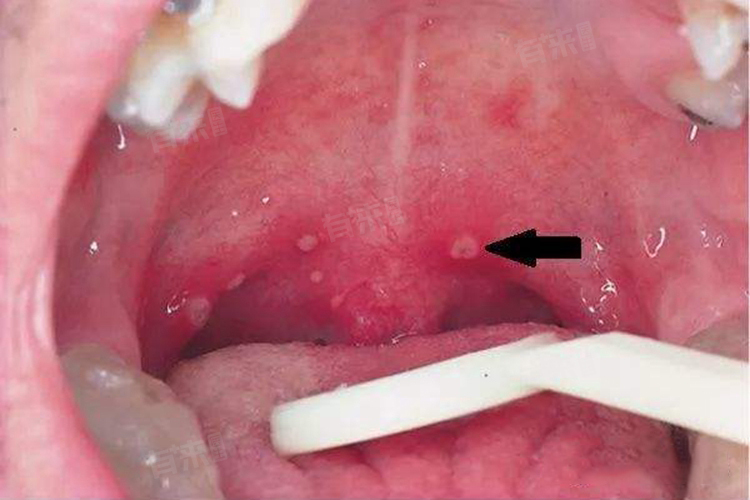

5、喉乳头状瘤:由人乳头瘤病毒感染引起,肿瘤呈白色乳头状突起,可单发或多发,可能出现声音嘶哑、喉部异物感等症状。治疗主要通过手术切除肿瘤,术后需定期复查,以防复发。